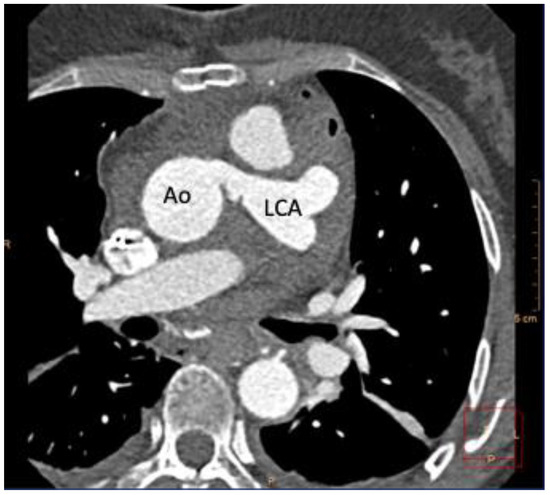

2. Case Report

Case Presentation